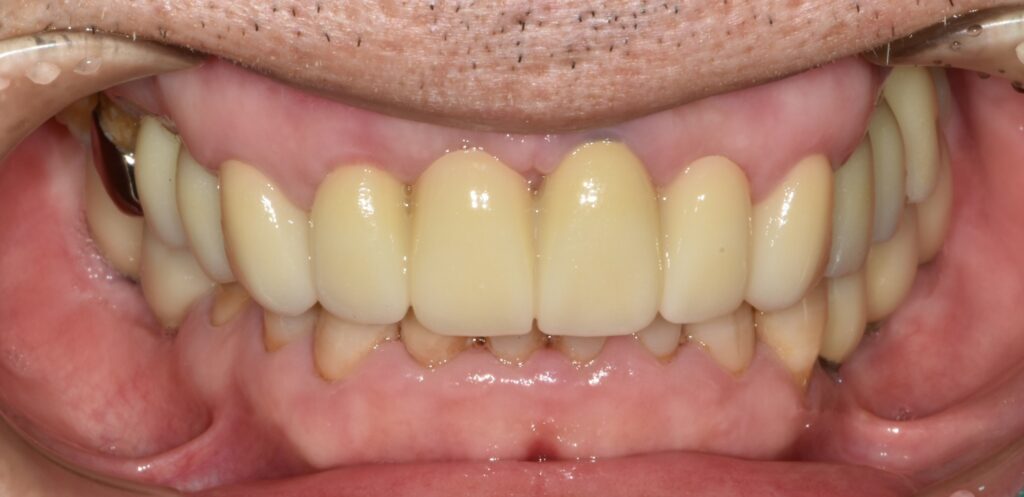

치료 완료

위와 같이 치료가 완료되었습니다. 깔끔하게 치료가 되었네요. 처음 상태와 비교해 보면 그 변화를 확실하게 느낄 수가 있습니다.

치료 기간은 대략 4개월 정도 소요되었습니다.

적절한 임플란트 치료를 통해서 씹는 즐거움도 되찾고 가지런한 치아로 자신감도 되찾으시길 바랍니다.